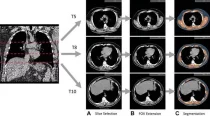

Пример полностью автоматизированной оценки состава тела при скрининге рака легких, неконтрастной низкодозной компьютерной томографии грудной клетки у 57-летнего мужчины. (A) […]… далее